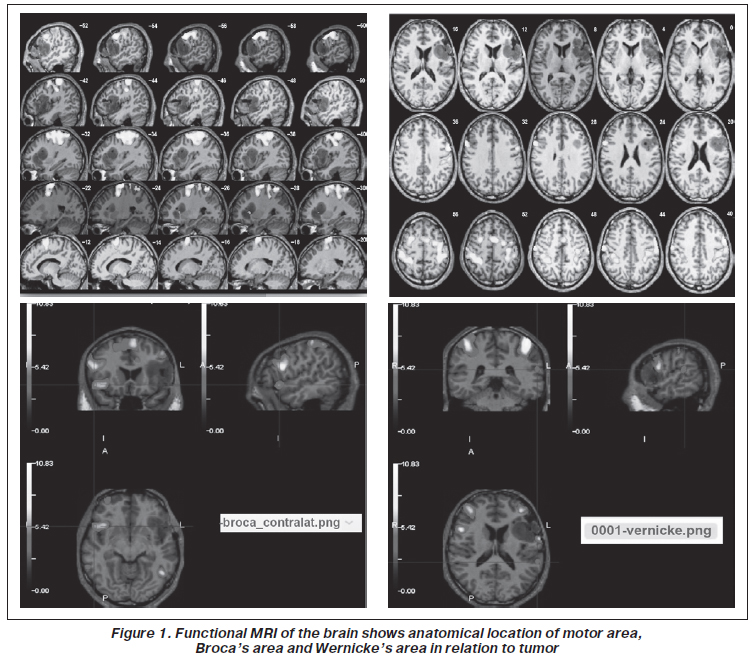

It has been a year since a 30-year-old male with no neurological condition began experiencing a partial seizure affecting the left arm and lower leg. On T1-weighted magnetic resonance images, large left fronto-parieto-temporal tumors were discovered in the Broca’s and Wernicke’s areas. The location of the Broca’s and Wernicke’s areas was determined using functional magnetic resonance imaging. The fMRI technique was used to better understand the position of the right hand’s motor center in relation to its anatomical location in the left hemisphere (Fig. 1).

/24.jpg)